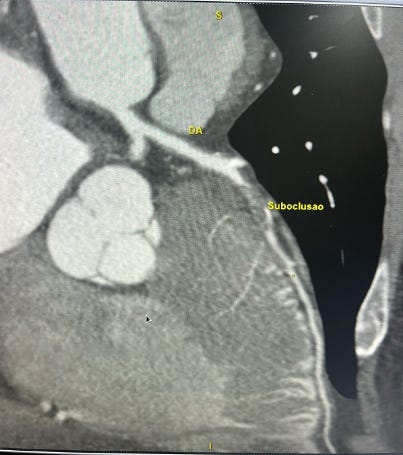

Imagem da semana

Coçou a mão aí também para colocar um stent rs?

Angiotomografia das coronárias que apresenta artéria descendente anterior difusamente doente com lesão suboclusiva no terço médio.